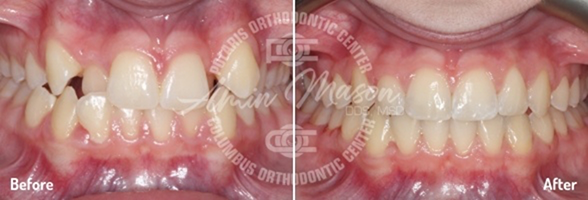

Case 1

Following teenage female patient visited our office with the chief complaint of “crooked teeth.” The patient expressed not being happy with her smile and was not eager to smile. They presented with mild class 2 occlusion, crowding of arches, and crossbite of maxillary lateral incisor teeth. The patient did not wish to have braces and requested clear aligners. She was treated with Invisalign clear aligners and elastics. Total treatment time was 26 months. Patient achieved excellent results.